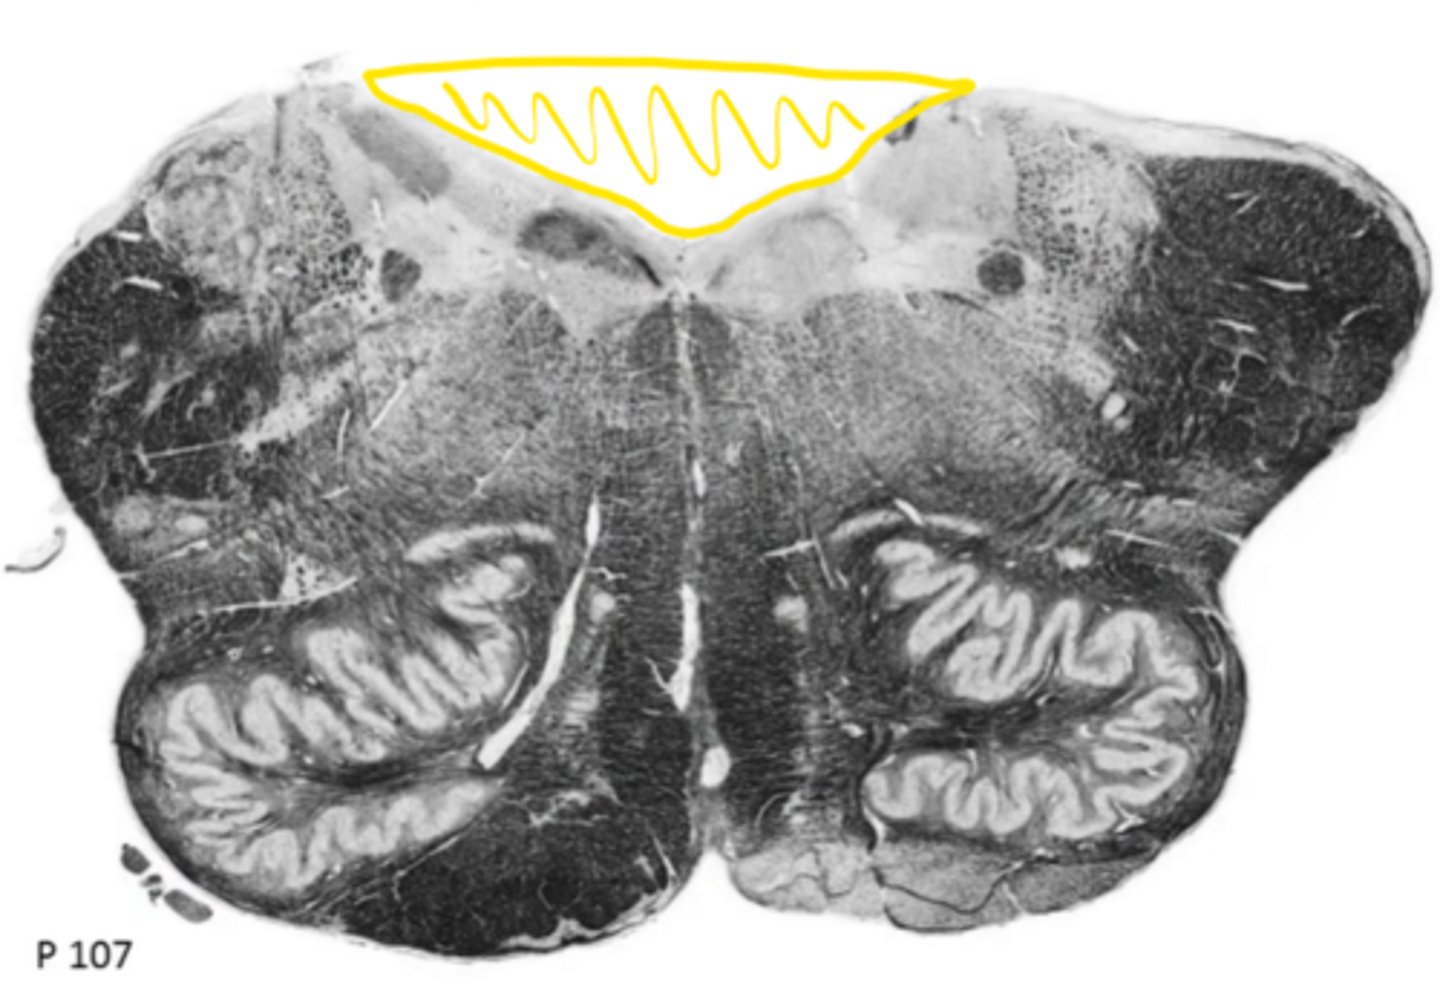

open medulla

ID the brainstem level